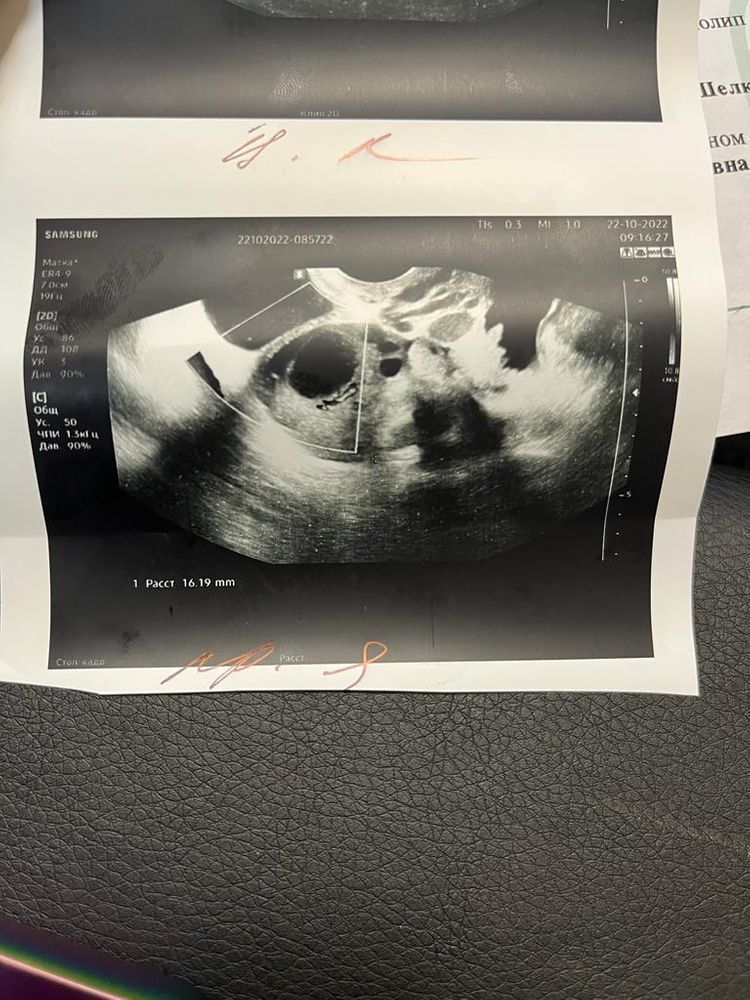

Изображение

Добрый вечер! Подскажите пожалуйста, делала узи фолликудометрии на 12 д.ц. правый яичник был доминантный 17 мм, па был на 13,14, д.ц. На 16 д.ц. узи показало чт